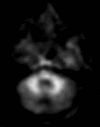

Neurodegenerative diseases are a devastating group of disorders that can be difficult to accurately diagnose. Although these disorders are difficult to manage owing to relatively limited treatment options, an early and correct diagnosis can help with managing symptoms and coping with the later stages of these disease processes. Both anatomic structural imaging and physiologic molecular imaging have evolved to a state in which these neurodegenerative processes can be identified relatively early with high accuracy. To determine the underlying disease, the radiologist should understand the different distributions and pathophysiologic processes involved. High-spatial-resolution MRI allows detection of subtle morphologic changes, as well as potential complications and alternate diagnoses, while molecular imaging allows visualization of altered function or abnormal increased or decreased concentration of disease-specific markers. These methodologies are complementary. Appropriate workup and interpretation of diagnostic studies require an integrated, multimodality, multidisciplinary approach. This article reviews the protocols and findings at MRI and nuclear medicine imaging, including with the use of flurodeoxyglucose, amyloid tracers, and dopaminergic transporter imaging (ioflupane). The pathophysiology of some of the major neurodegenerative processes and their clinical presentations are also reviewed; this information is critical to understand how these imaging modalities work, and it aids in the integration of clinical data to help synthesize a final diagnosis. Radiologists and nuclear medicine physicians aiming to include the evaluation of neurodegenerative diseases in their practice should be aware of and familiar with the multiple imaging modalities available and how using these modalities is essential in the multidisciplinary management of patients with neurodegenerative diseases.©RSNA, 2020.